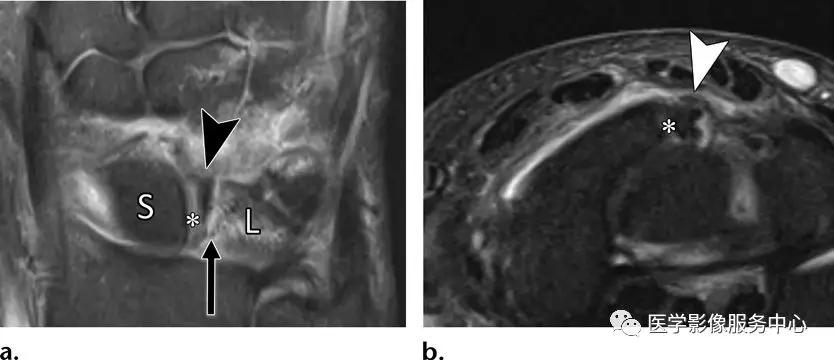

舟月韧带的撕脱损伤:

(左)月骨的撕脱骨片(黑色箭头),伴高信号的骨折线(黑色长剪头)。舟月韧带完整,连接于月骨的骨碎片(*)及舟骨(S)。月骨(L)的桡侧半部分可见反应性骨髓水肿。(右)月骨的骨碎片(白色箭头)连接于完整的舟月韧带(*)。